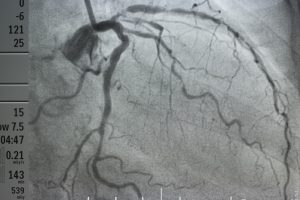

Ore, reagoni për këtë. Reagoni të paktën për shëndetësinë, për shëndetin tuaj se nesër pastaj do e paguani ju, familjarët tuaj, fëmijët tuaj, gjyshërit tuaj, të gjithë, e gjithë ne me radhë, mo. E na ruajt Zoti, unë e them, sidomos për këtë trombektominë, e arteriografinë, na ruajt Zoti, se po na ra Flavio, shans ne nuk kemi.